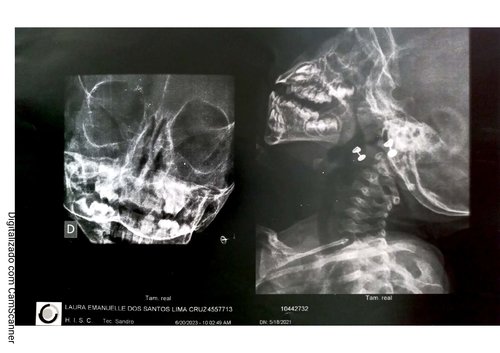

Eu sou a Hellen e criei essa vaquinha para ajudar à Laura Emanuelle, neta de um amigo, Arineu. A Laura tem dois aninhos e sofre com estreitamento do canal respiratório e glândulas aumentadas, causando obstrução nasal. Ela precisa passar por uma cirurgia chamada adenoidectomia, no valor de 12.000 reais, para conseguir respirar normalmente. A mãe deixou o emprego para cuidar da Laura, que tem uma saúde frágil devido à sua condição.

Seguem abaixos exames e comprovantes do estado médico da Laurinha: